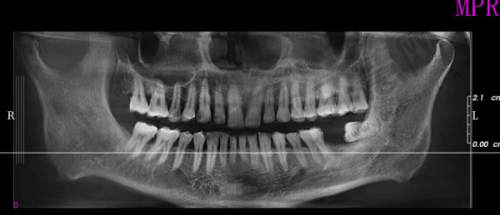

规模与营业时间:北京欢乐将臣口腔门诊部预设工作人员12人,设有8张牙椅,全年营业360天,每天营业时间为9:00 - 18:00 。科室设置与诊疗优势:诊疗科目包括口腔科和医学影像科的X线诊断专精。口腔科作为核心科室,可开展牙齿修复、牙齿美白、正畸等多种常见口腔疾病的诊断和治疗。医学影像科的X线诊断专精借助精良设备,为口腔疾病精细诊断提供有力支持,帮助医生制定科学有效的治疗方案,为患者提供全方面、个性化的口腔诊疗服务。